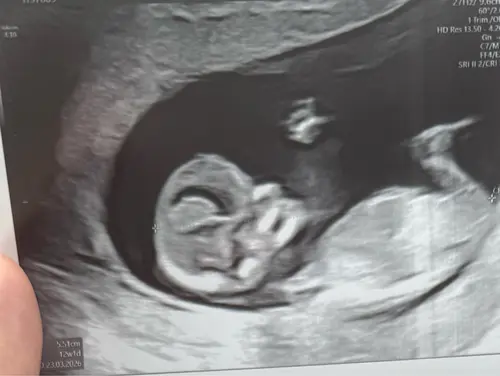

Weten jullie naar welke cirkel ik moet kijken? Dit is een 13,2 weken echo (tussen de beentjes) Bovenste lijken 2 streepjes van een meisje en daar onder lijkt een piemeltje.

Ik had bij mijn echo ook zo’n streep waardoor ik denk een jongen, maar als ik dan pottyshot foto’s zie van andere babies bij dezelfde termijn dan is het toch echt bij andere al beter te zien als het een jongen is.

Dus ik ben bang dat je nog een aantal weken moet wachten tot je zekerheid hebt 😅. Ga je een geslachtsbepalingsecho doen?